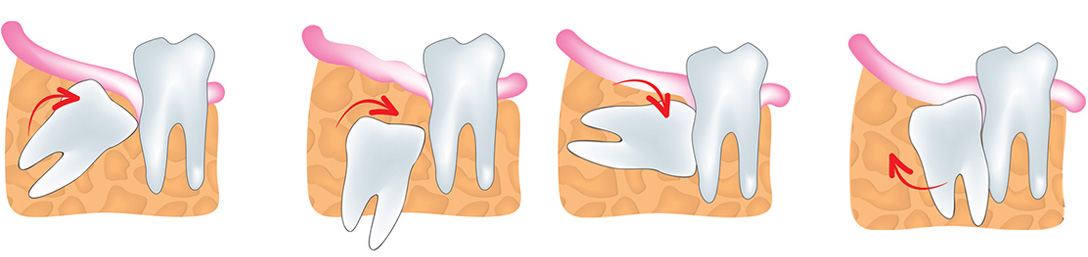

Once the patient is numb from the neighborhood sedative and the required x-beams have been taken, the dental specialist starts the particular piece of the method by evacuating the gum tissue that is covering the region where the insight tooth is found. If the shrewdness tooth is affected, an entry point is made in the gum tissue, to get to the tooth. The gum tissue is then pushed off the beaten path with a particular instrument until the point that the tooth is visible. There is a decent possibility that an affected shrewdness tooth could be entirely or halfway canvassed in the bone. On the off chance that there is bone covering the wisdom teeth, an electric handpiece is utilized to penetrate through and evacuate the bone comprising the tooth. If the wisdom tooth has just emitted into your mouth, the dental specialist will extricate the connective tissue from around the shrewdness tooth.

Once the affected insight teeth are apparent to the dental specialist, different careful instruments are utilized to tenderly slacken the knowledge tooth from any connective tissue in the tooth’s attachment. The utilization of the electric handpiece might be used on and off all through the extraction. A similar methodology applies to an intelligence tooth that was at that point ejected. It might be essential for the dental practitioner to cut the tooth into segments before it is evacuated. This is done because the tooth is in danger for breaking while it is being expelled from the attachment.